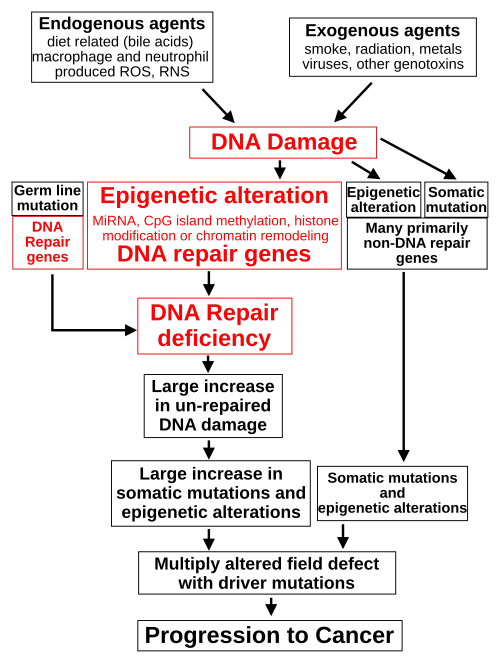

Epigenetics

The classical view of cancer is a set of diseases driven by progressive genetic abnormalities that include mutations in tumor-suppressor genes and oncogenes, and in chromosomal abnormalities. A role for epigenetic alterations was identified in the early 21st century.[103]

Epigenetic alterations are functionally relevant modifications to the genome that do not change the nucleotide sequence. Examples of such modifications are changes in DNA methylation (hypermethylation and hypomethylation), histone modification[104] and changes in chromosomal architecture (caused by inappropriate expression of proteins such as HMGA2 or HMGA1).[105] Each of these alterations regulates gene expression without altering the underlying DNA sequence. These changes may remain through cell divisions, endure for multiple generations, and can be considered as equivalent to mutations.

Epigenetic alterations occur frequently in cancers. As an example, one study listed protein coding genes that were frequently altered in their methylation in association with colon cancer. These included 147 hypermethylated and 27 hypomethylated genes. Of the hypermethylated genes, 10 were hypermethylated in 100% of colon cancers and many others were hypermethylated in more than 50% of colon cancers.[106]

While epigenetic alterations are found in cancers, the epigenetic alterations in DNA repair genes, causing reduced expression of DNA repair proteins, may be of particular importance. Such alterations may occur early in the progression to cancer and are a possible cause of the genetic instability characteristic of cancers.[107][108][109]

Reduced expression of DNA repair genes disrupts DNA repair. This is shown in the figure at the 4th level from the top. (In the figure, red wording indicates the central role of DNA damage and defects in DNA repair in the progression to cancer.) When DNA repair is deficient DNA damage remains in cells at a higher than usual level (5th level) and causes increased frequencies of mutation and/or epimutation (6th level). Mutation rates increase substantially in cells defective in DNA mismatch repair[110][111] or in homologous recombinational repair (HRR).[112] Chromosomal rearrangements and aneuploidy also increase in HRR defective cells.[113]

Higher levels of DNA damage cause increased mutation (right side of figure) and increased epimutation. During repair of DNA double strand breaks, or repair of other DNA damage, incompletely cleared repair sites can cause epigenetic gene silencing.[114][115]

Deficient expression of DNA repair proteins due to an inherited mutation can increase cancer risks. Individuals with an inherited impairment in any of 34 DNA repair genes (see article DNA repair-deficiency disorder) have increased cancer risk, with some defects ensuring a 100% lifetime chance of cancer (e.g. p53 mutations).[116] Germline DNA repair mutations are noted on the figure's left side. However, such germline mutations (which cause highly penetrant cancer syndromes) are the cause of only about 1 percent of cancers.[117]

In sporadic cancers, deficiencies in DNA repair are occasionally caused by a mutation in a DNA repair gene but are much more frequently caused by epigenetic alterations that reduce or silence expression of DNA repair genes. This is indicated in the figure at the 3rd level. Many studies of heavy metal-induced carcinogenesis show that such heavy metals cause a reduction in expression of DNA repair enzymes, some through epigenetic mechanisms. DNA repair inhibition is proposed to be a predominant mechanism in heavy metal-induced carcinogenicity. In addition, frequent epigenetic alterations of the DNA sequences code for small RNAs called microRNAs (or miRNAs). miRNAs do not code for proteins, but can "target" protein-coding genes and reduce their expression.

Cancers usually arise from an assemblage of mutations and epimutations that confer a selective advantage leading to clonal expansion (see Field defects in progression to cancer). Mutations, however, may not be as frequent in cancers as epigenetic alterations. An average cancer of the breast or colon can have about 60 to 70 protein-altering mutations, of which about three or four may be "driver" mutations and the remaining ones may be "passenger" mutations.[118]